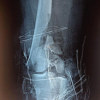

In the trauma bay, the patient complained of the right hip and leg pain and was found to have associated shortening and deformity of the extremity. There was a 2 cm × 1 cm open laceration over the distal tibia with exposed bone fracture fragments. The patient was intubated for airway protection and radiographs were obtained of the right hip, femur, and lower leg demonstrating a right hip fracture dislocation with associated right femoral and tibial shaft fractures (Fig. 1-3).

Computed tomography (CT) scan of the pelvis further delineated the posterosuperior hip dislocation with associated fractures of the posterior wall of the acetabulum and femoral head (Fig. 4).

Attempts in the emergency department to obtain a closed reduction of the hip dislocation were unsuccessful due to difficulty posed by her femur and tibia fractures. To reduce the hip and minimize the risk of developing AVN, she was taken urgently to the operating room for surgical management. In the operating room, the patient was placed supine on a radiolucent table with a small bump underneath the right buttock. Given the nature of her hip injury, priority was given to the reduction of the hip dislocation. A 5 mm Schanz pin was placed percutaneously along the axis of the femoral neck (Fig. 5).

Traction and gentle rotation were applied to reduce the femoral head back into the acetabulum (Fig. 6) and an inferior infrafoveal femoral head impaction fracture was confirmed.

Next, the open tibia fracture was debrided, closed primarily and both the tibia and femoral shaft fractures were treated with intramedullary nails (Fig. 7-9).